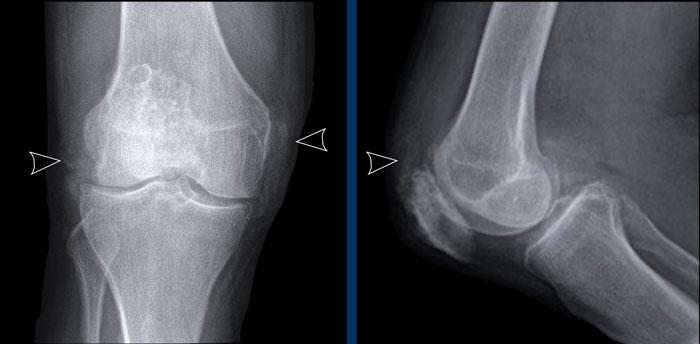

F

Thoái hóa khớp gối

Hẹp khe khớp đùi-chày khoang trong mức độ vừa đến nặng, không đối xứng, kèm hình thành gai xương và xơ cứng xương dưới sụn (phân loại Kellgren-Lawrence độ 3-4).